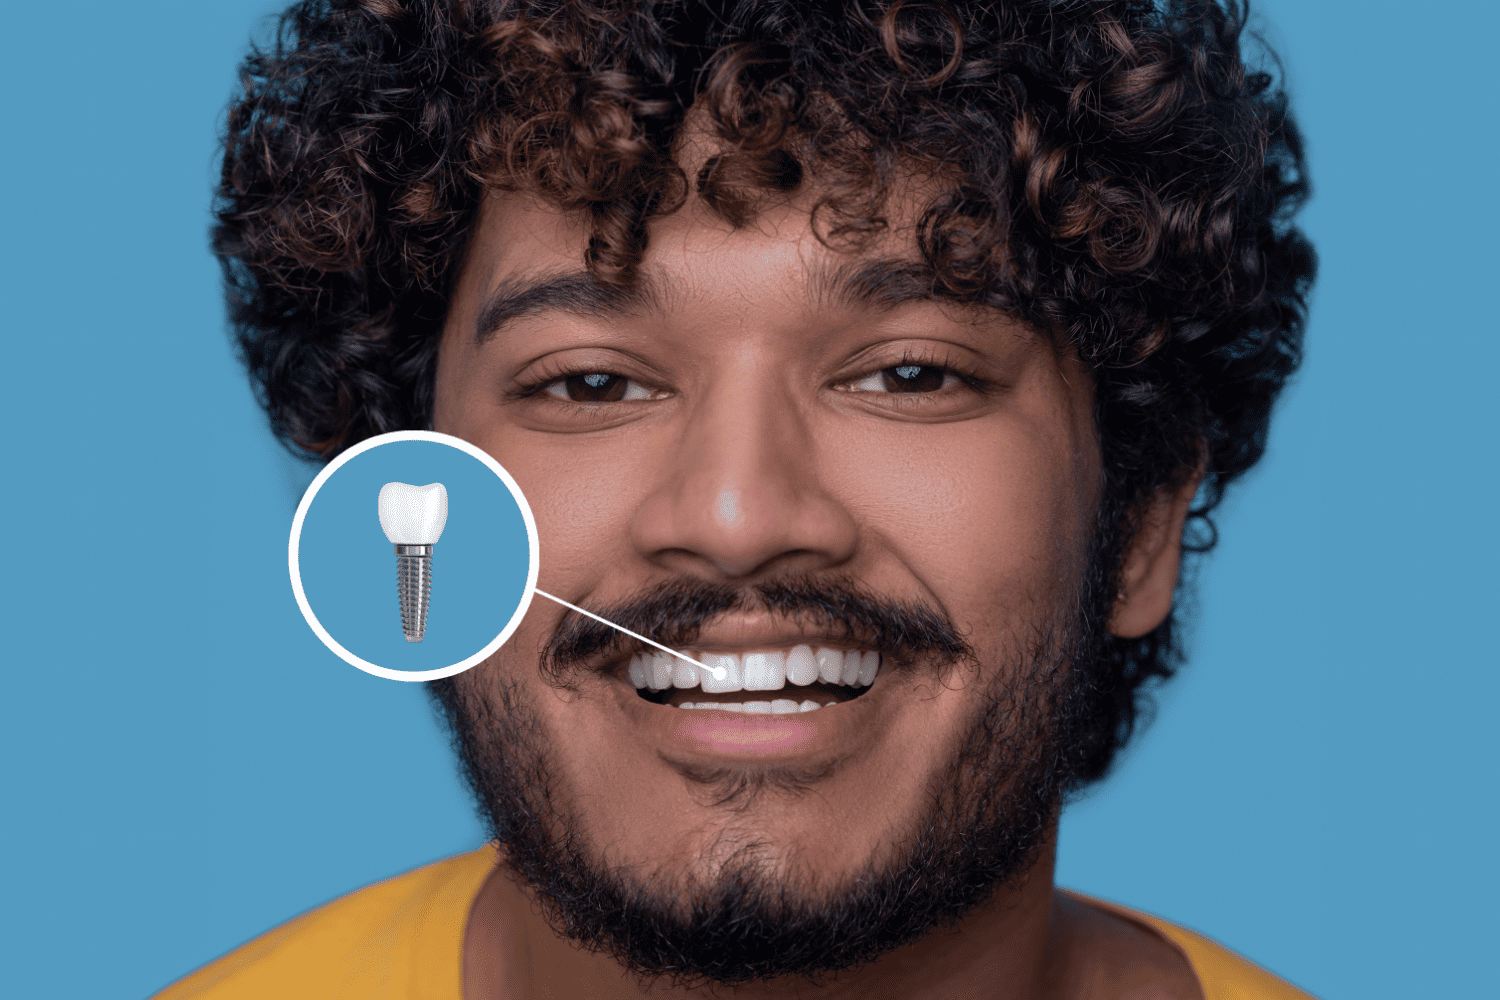

READ MOREDental Implants in Jaipur Services Crowns Bridges Dentures...